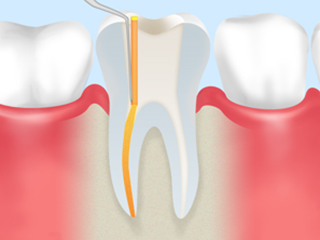

step4

根管内のすみずみまで薬剤を充填し、隙間ができないように密封します。